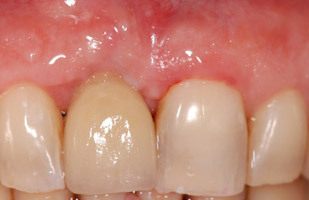

- Cas 1:

Dans une volonté de discrétion et de naturel, le patient a demandé que la couronne sur implant soit aussi jaune que la dent naturelle remplacée